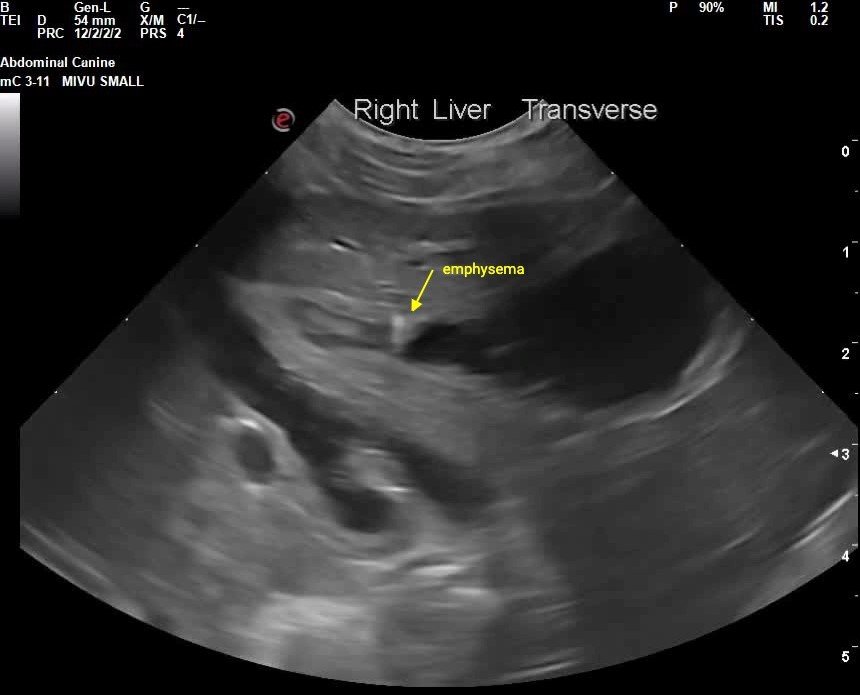

The gallbladder is moderately distended with anechoic and dense hyperechoic organizing bilious sludge adhering to the gallbladder wall. The gallbladder wall appears thickened with areas of severely hyperechoic comet-tails concerning for emphysematous cholecystitis. Significant common bile duct dilation is seen, with a maximum diameter of approximately 0.5 cm. The gallbladder is diffusely severely dilated to the level of the major duodenal papilla. A homogenous hyperechoic mass in the region of the major duodenal papilla measures approximately 0.4 cm in diameter.

Image 6: Sagittal view of the gallbladder showing suspected gas infiltration of the gallbladder wall. Emphysematous cholecystitis is likely a sign of severity of infection in the gallbladder.